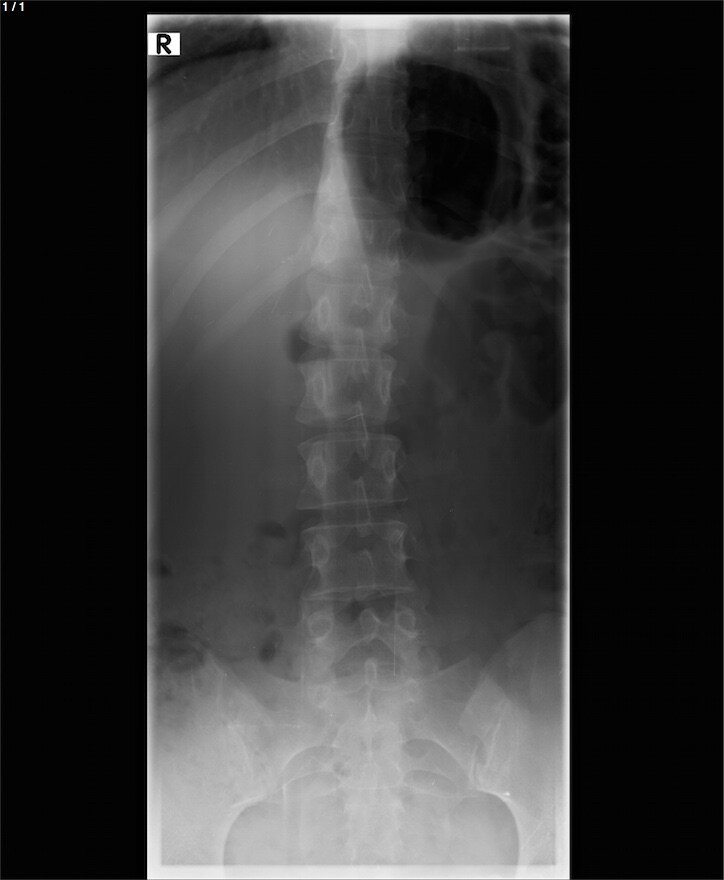

Кто разбирается в рентгеновских снимках, подскажите, здесь есть перелом крестца? Если есть, подскажите, куда конкретно смотреть?

Снимок крайне плохого качества и на данном снимке однозначно ответить на вопрос о переломе крестца невозможно.  В данном  случаи интерпретировать данный снимок сможет врач травматолог или рентгенолог.